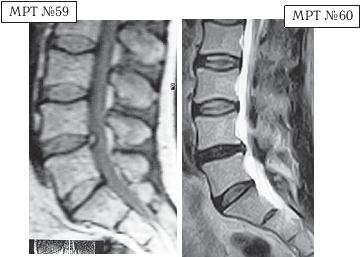

СКТ № 1

На спиральной компьютерной томографии (СКТ) № 1 наблюдается сращение между собой поперечных отростков LIII-LIV

СКТ № 2

На СКТ № 2 наблюдается аномальное слияние поперечногоотростка пятого поясничного позвонка с крестцом — сакрализация.